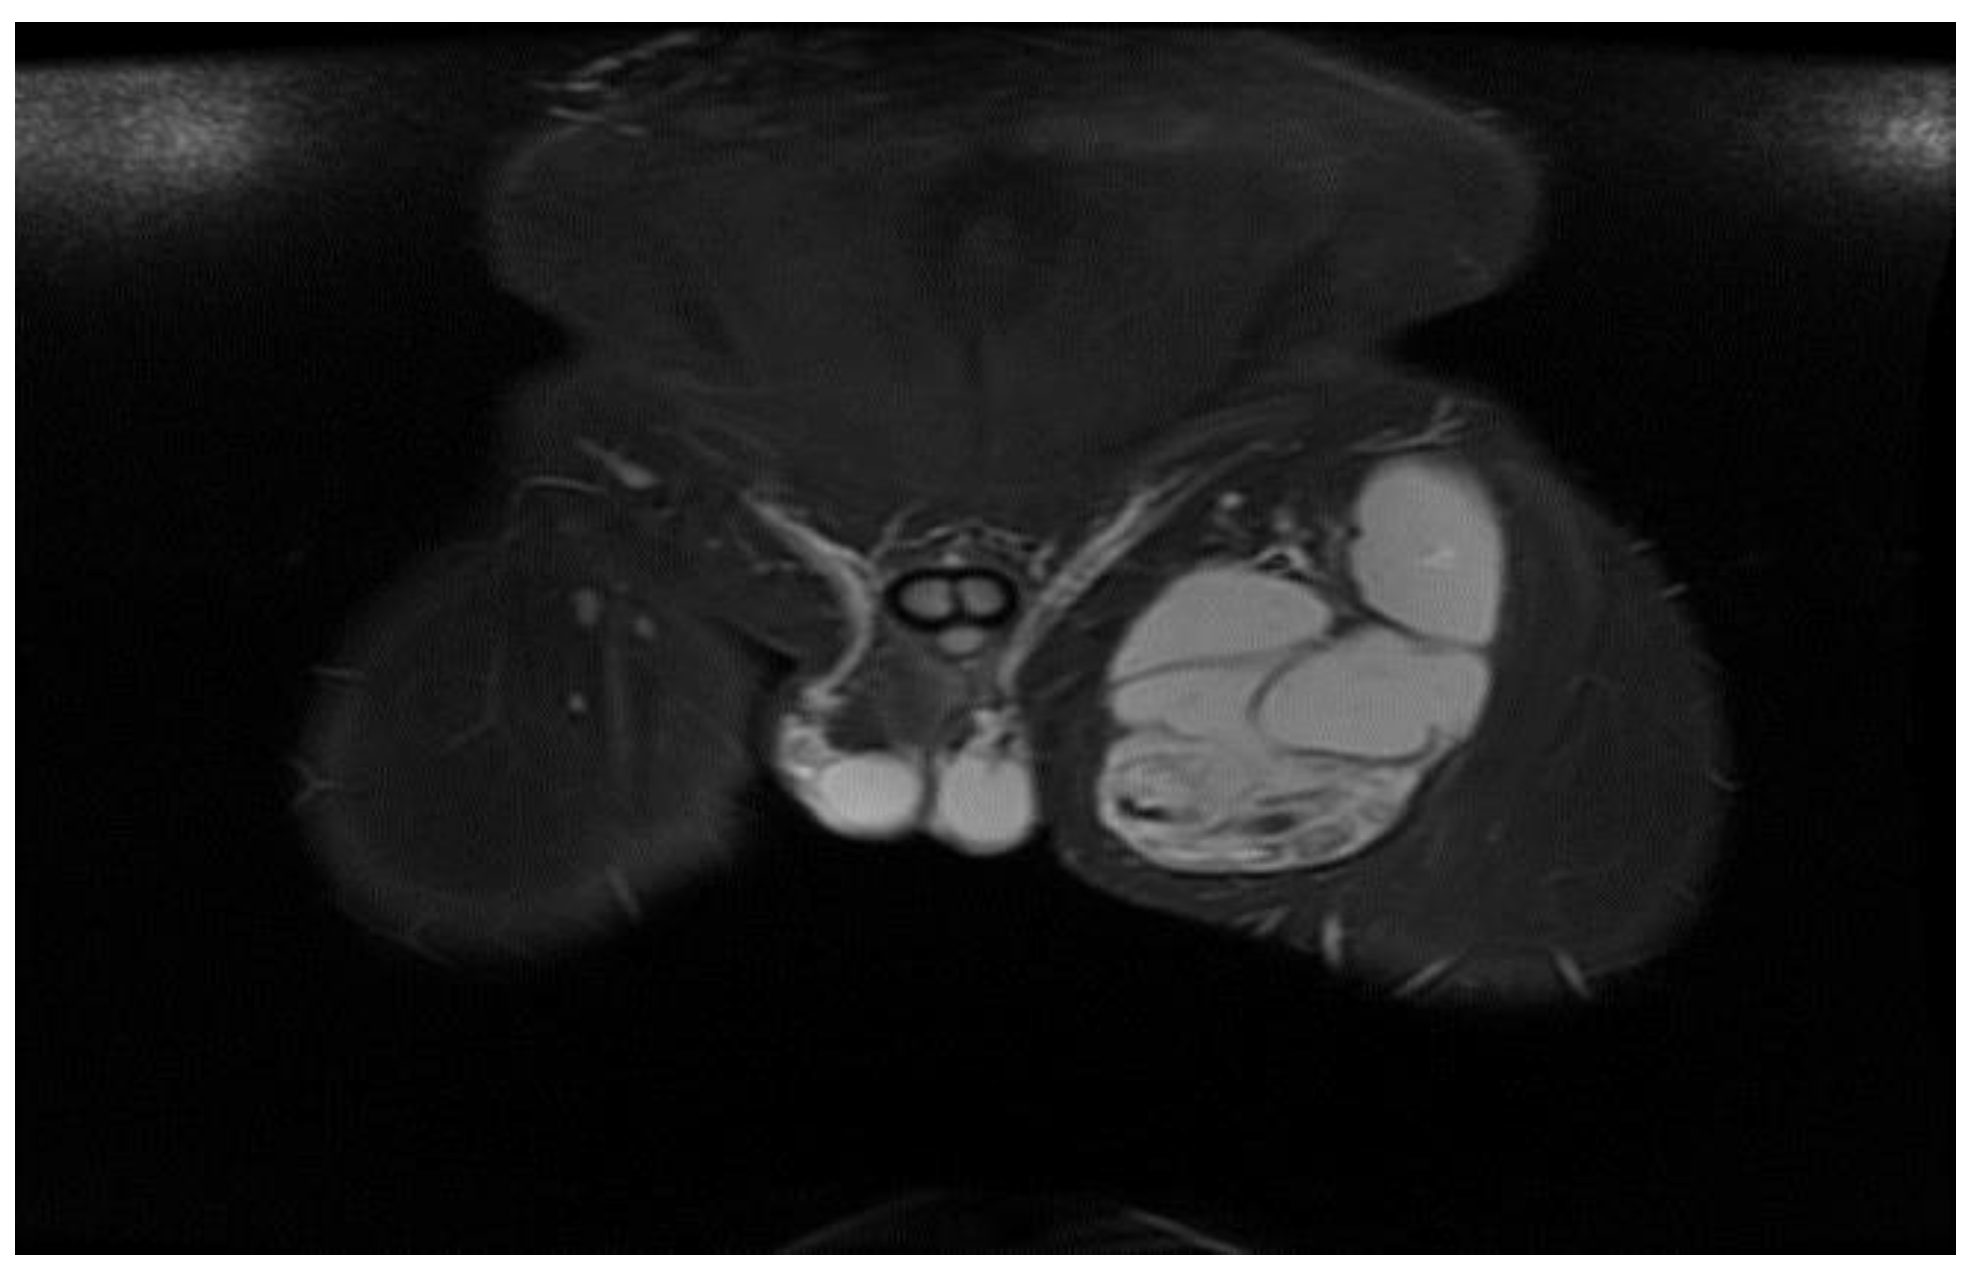

Figure 20.

T2W sequence, axial—Postoperative residual hydatid cyst located at the level of the left psoas muscle and deep to the left gluteus maximus muscle (part 1).

Deep from the gluteus maximus muscle on the left side, there are multiloculated, multiple septate intralesional, relatively well delimited areas, which seem to communicate both with each other and with lesions of a similar appearance located in the thickness and adjacent to the quadratus femoris muscle on the left side, with total dimensions in the coronal plane of approximately 11.3/6.4 cm, with the most likely appearance of parasitic cysts (Figure 19, Figure 20 and Figure 21).